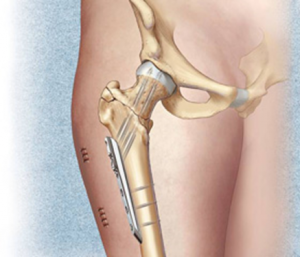

Ұршық асты және айдаршық үсті сынықтарының остеосинтезі үшін жиі бұрышты пластина немесе накладкасы бар динамикалық винт қолданылады. Ортаңғы үштен бір бөлігінің сынығында пластинамен экстрамедуллярлы остеосинтез немесе штифпен интрамедуллярлы остеосинтез жүргізіледі. Стерженьдік аппарат көмегімен фиксациялауға да болады.

Диафиз сынығының стабильды остеосинтезңне құм сағаты формалы сүйекми каналының біркелкі емес ені бөгет жасайды. Штифт тек қана каналдың арылу аймағында ғана жанасып жатады. Егер сынық аймағына сүйекми каналының тарылу аймағы сәйкес келмесе сынықшалар арасында ротационды және тербелмелі қозғалыстар тән. Стабильді остеосинтез жасау үшін сынық орнында сүйекми каналын штифтпен бірдей қылып бұрғылайды. Сәйкес диамитрлі штифт енгізіледі. Бұрғылаусыз стабильды остеосинтез үшін дистальды және проксимальды блоктайтын штифт қолданылады.

Стабильді остеосинтезден кейін гипстік таңу салынбайды. Операциядан кейін бірінші күндері аяққа дозирленген жүктемемен балдақпен жүруге болады. Толық жүктемені сынық сипаты мен фиксатор түріне байланысты рұсат етіледі.